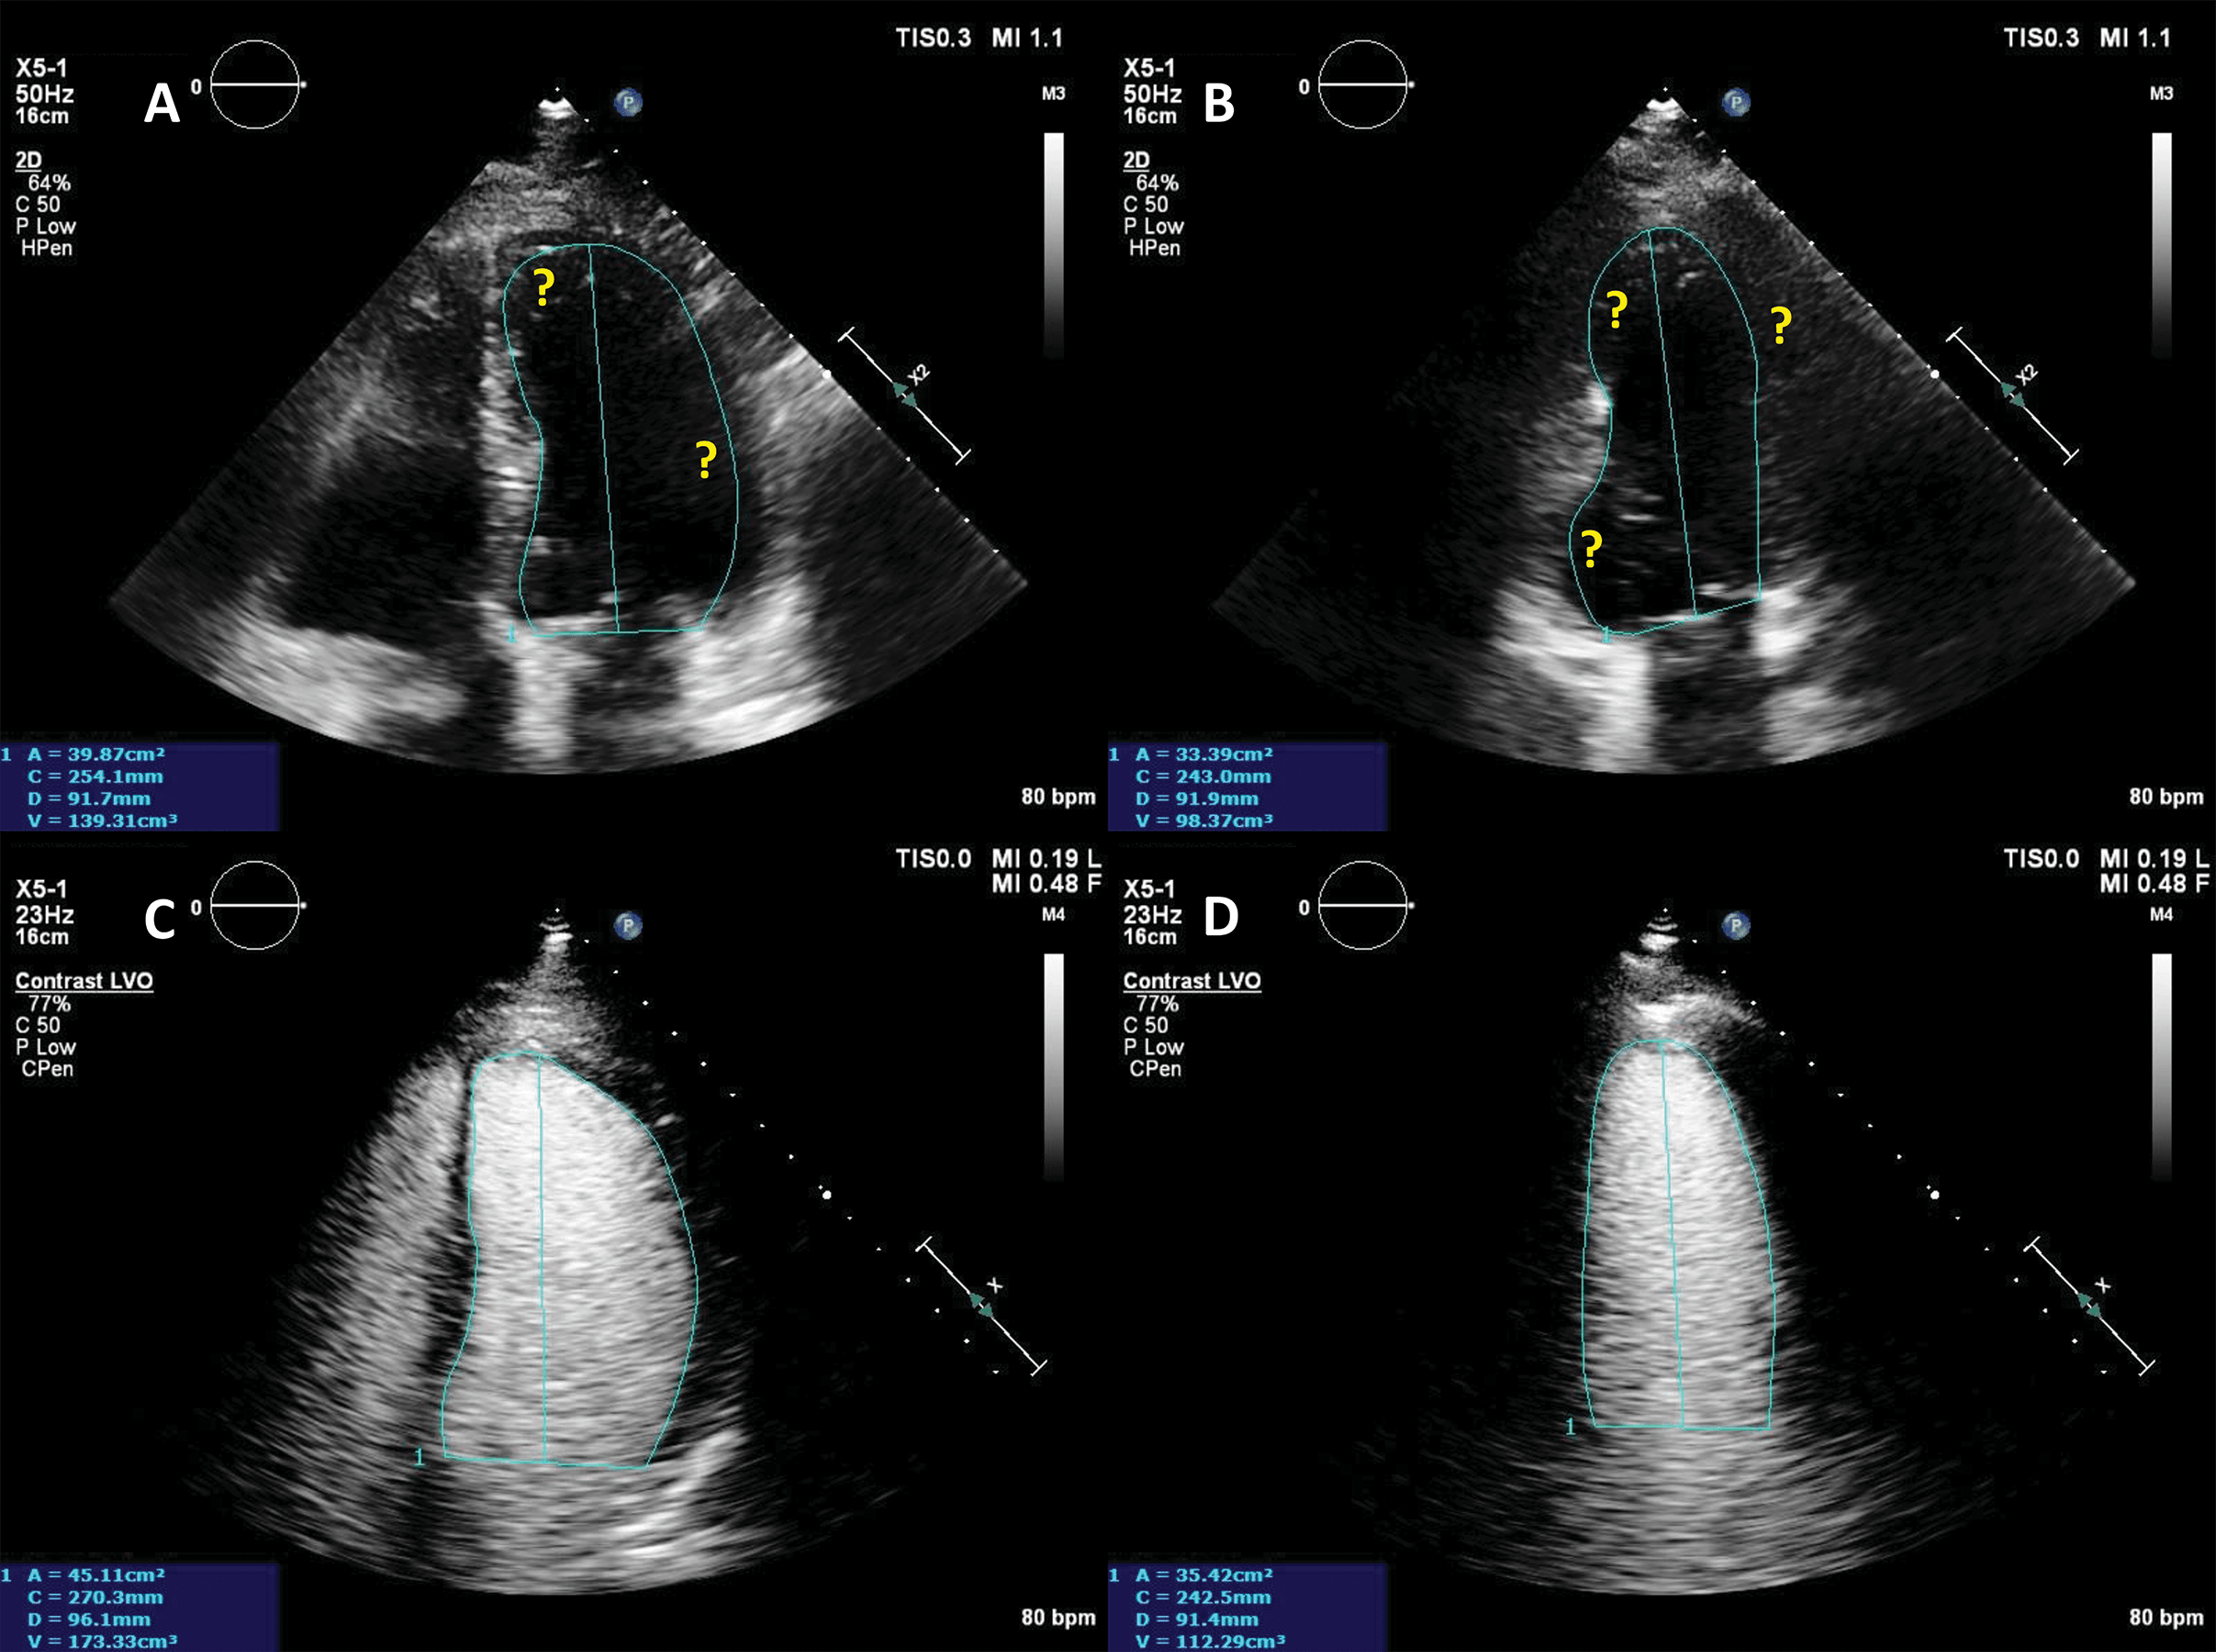

Another application of LVO is morphological diagnosis, particularly in disease states which manifest in the artefact-prone LV apex. Beside possible foreshortening, the LV apex is prone to clutter and reverberation artefacts, while also having a weaker potential to generate harmonics because of its position in the near-field in apical views [28]. As such, apical forms of hypertrophic cardiomyopathy [29, 30], eosinophilic cardiomyopathy [31] and non-compaction cardiomyopathy [32] may escape detection with unenhanced ultrasound.

Numerous case reports and case series document the use of UEA in these instances [29, 30, 31, 32, 33]. Studies have also been performed demonstrating the added value of contrast-enhanced ultrasound in hypertrophic cardiomyopathy [34] (Fig. 4, Video 4).

Fig. 4.Hypertrophic cardiomyopathy patient with very poor image in apical 4-chambers view. (A,B) Native images, end-diastole (A) and end-systole (B). The endocardium of the lateral wall is not visible, and the apex cannot be seen. (C,D) Contrast-enhanced images, in the same moments in the cardiac cycle. The LV contour is clearly delineated, during systole there is complete cavity obliteration, with an apical aneurysm (arrow). Source: personal collection.